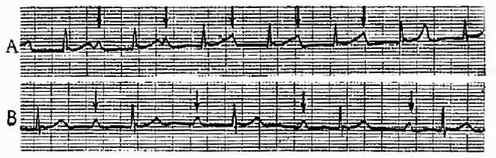

一、第一度房室传导阻滞 ①P-R间期>0.20秒,②每个P波后,均有QRS波群。(图3-3-19)

图3-3-19 第一度房室传导阻滞

(一)第二度Ⅰ型传导阻滞-文氏现象①P-R间期逐渐延长,直至P波受阻与心室脱漏,②R-R间期逐渐缩短,直至P波受阻;③包含受阻P波的R-R间期比两个P-P间期之和为短。(图3-3-20)

图3-3-20 Ⅱ度Ⅰ型房室传导阻滞(文氏现象)